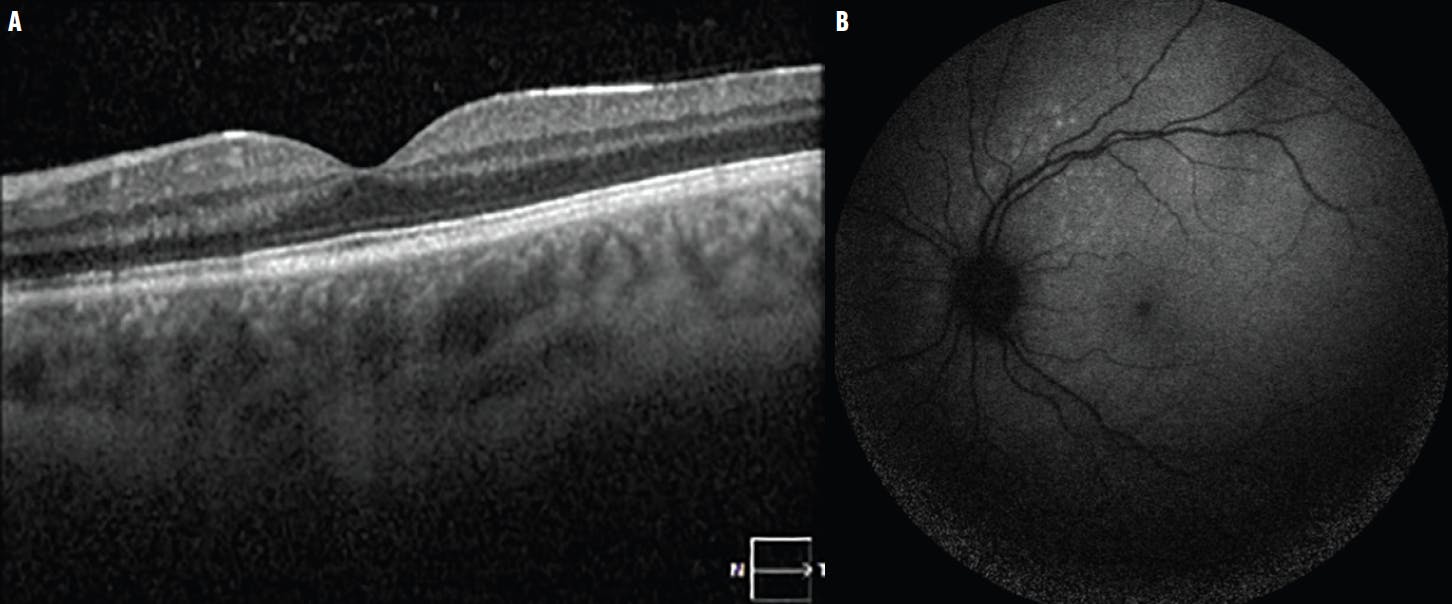

At follow-up 11 days later, the patient reported a decrease in his peripheral scotoma in the left eye and improved vision. Examination showed a decrease in the prominence and number of the deep retinal yellow lesions. At 2 months, OCT demonstrated reconstitution of the ellipsoid zone, and FAF showed a decrease in the size and intensity of the hyperfluorescence (Figure 4). He was advised to continue the planned prednisone taper.

<p>Figure 4. At the 2-month follow-up, the left eye presented with reconstitution and partial recovery of the ellipsoid zone on OCT (A), as well as decreased intensity of hyperautofluorescence on FAF (B).</p>

Figure 4. At the 2-month follow-up, the left eye presented with reconstitution and partial recovery of the ellipsoid zone on OCT (A), as well as decreased intensity of hyperautofluorescence on FAF (B).